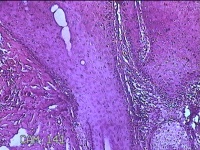

头部肿物

性别

男

年龄

21岁

临床诊断

头皮肿物

一般病史

发现头部结节10余年,无明显疼痛及不适。

标本名称

头部结节

大体所见

灰白暗红色带皮肤样结节1.5x1.3x0.3cm一个,切开结节呈实性,切面灰白粉红色,质软。